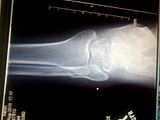

now heres the mystery one. well it was to me. im wondering why this thing hurts like it does and i cant see anything obvious. a moment of divine inspiration later, get a strong urging to read the reports. classified as an "oblique aortic distal fracture of the tibia". ( main weight bearing bone) heres the aha moment if i could find one lol "diagnosed by the widening of the space between the tibula and fibula and fractures in a vertical plane. gap is obvious. that much space? errm not sposed to be like this. long story short is my left leg is trying to split apart like a wishbone lol anyhoo  the pic. ( you will see the gap) btw it is sfw:

correction i misquoted term for the i dont see it fracture. it is whats known as a "oblique aortic fracture of lateral aspect of distal tibia " i.e. the tib and fib should be joined/touching. not spread apart. swelling is all but gone. except where the fib is spread out, its a tad noticeable. almost afraaid to remove airboot. was fine earlier when i would do this now its omg. something aint right. only been 3 weeks still though. going to try making it through night and see what its like first thing. and go from there. beyond that i should have read into this earlier. my own fault. for not listening to common sense :(